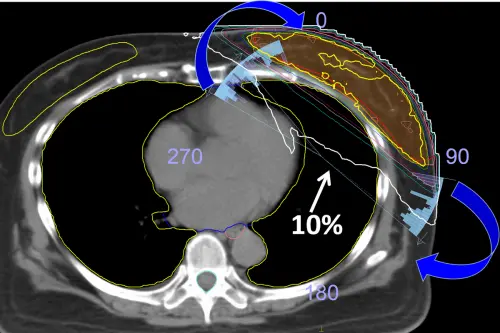

▲以小角度動態調控射束方向(藍色圓弧),可將治療劑量集中在腫瘤區域,有效保護心、肺。(圖/台北慈院提供) 針對「雙光子影像導引系統」,黃經民說明,其整合交叉影像與體表導航技術,治療時透過2組高畫質X光定位腫瘤,並以光點及熱感技術掃描病人體表,可即時調整體位和射束方向,提升治療準確性;相較於傳統方式,這項技術不必在皮膚標記,能有效減少誤差和劑量,也可強化病人隱私保護與整體體驗。

此外,黃經民指出,台北慈濟團隊同步開發短弧度乳房照射技術,選用較小角度弧形路徑,將放射線集中於腫瘤區域,減少對側乳房與心、肺的劑量負擔,這對左側乳癌病人特別重要,有助於降低日後發生放射性肺炎或心血管併發症的風險。